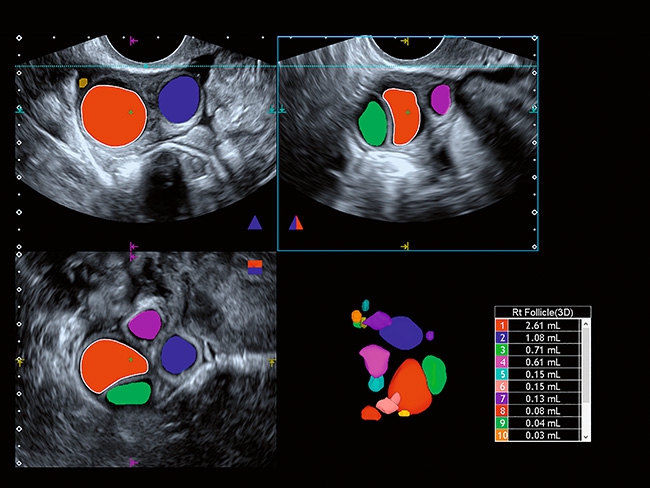

Отличная цветопередача с высокой детализацией и четкостью изображения. Устройство подходит для профессионального использования в частных кабинетах и крупных медицинских центрах. Комплектация сканера применима для самых разных исследований. Широкий диапазон прикладного клинического программного обеспечения высокоэффективен для общих исследований, сердечно-сосудистых, гинекологических, ортопедических, урологических.

Aplio a550 может работать с линейным матричным датчиком и поддерживает новейшие монокристаллические датчики. Также Aplio a550 поддерживает большое количество дополнительных опций, таких как - SMI, Компрессионная эластография, Эластография сдвижной волны, Smart Fusion, исследования с использованием контраста (CEUS), 3D реконструкции в реальном времени (4D), функции автоматической оценки подвижности миокарда и фракции выброса.

Гинекология:

Да